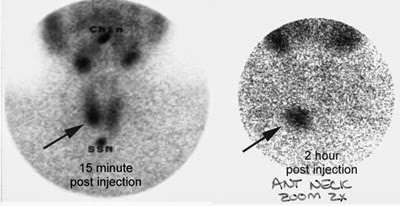

Το σπινθηρογράφημα παραθυρεοειδών με Sestamibi. Στο ειδικό αυτό Σπινθηρογράφημα με sestamibi ο ασθενής λαμβάνει μια πολύ μικρή ποσότητα μιας ραδιενεργούς ουσίας, η οποία απορροφάται μόνο από τον υπερλειτουργούντα παραθυρεοειδή αδένα και μας οδηγεί στον εντοπισμό του.